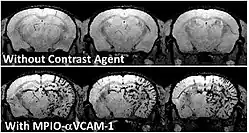

To achieve molecular imaging of disease biomarkers using MRI, targeted MRI contrast agents with high specificity and high relaxivity (sensitivity) are required. To date, many studies have been devoted to developing targeted-MRI contrast agents to achieve molecular imaging by MRI. Commonly, peptides, antibodies, or small ligands, and small protein domains, such as HER-2 affibodies, have been applied to achieve targeting. To enhance the sensitivity of the contrast agents, these targeting moieties are usually linked to high payload MRI contrast agents or MRI contrast agents with high relaxivities.[2] In particular, the recent development of micron-sized particles of iron oxide (MPIO) allowed to reach unprecedented levels of sensitivity to detect proteins expressed by arteries and veins.[3]